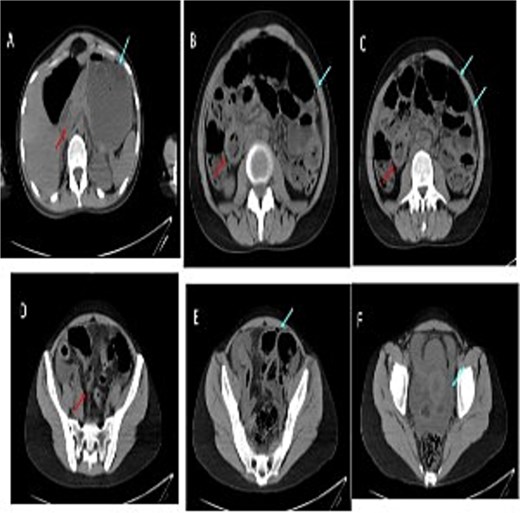

Cross-sectional imaging of the abdomen demonstrated findings concerning for small bowel perforation (Fig. 1). Given the clinical and radiologic evidence of peritonitis, urgent surgical exploration was performed. Intra-operatively, a perforated segment of distal ileum with adjacent inflamed mesentery was identified (Fig. 2). Limited resection of the affected ileal segment, including associated mesentery and regional lymph nodes, was undertaken. A functional side-to-side stapled anastomosis was created, and a proximal diverting loop ileostomy was fashioned to reduce the risk of anastomotic complications.

Serial images from the patient computed tomography abdominal scan that showed terminal ileum wall thickening contributing to luminal narrowing, along with surrounding fat stranding and mesenteric congestion which is associated with some adjacent prominent lymph nodes. There is few foci of extraluminal free gas reflecting bowel perforation, in addition to free fluid in the pelvis and paracolic gutters. Despite the presence of some bowel dilatation no complete bowel obstruction and the rectum lumen is preserved.

Fat creeping, ileal perforation, lymph nodes (mesenteric lymphadenitis).